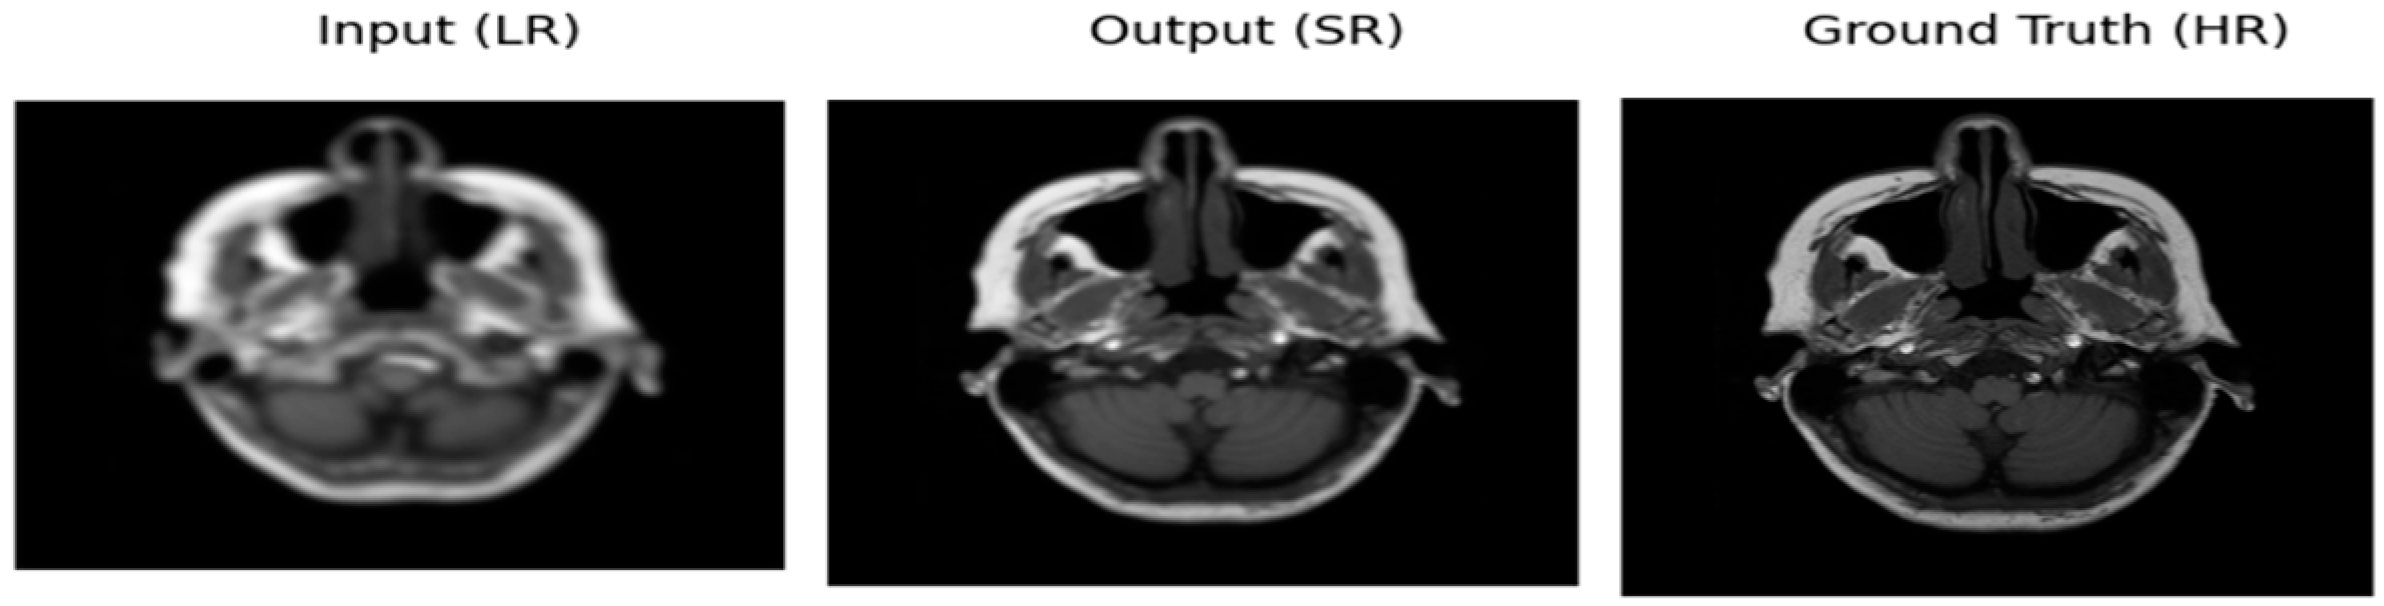

3.2. Performance of ADAM Optimizer and Use of Loss Functions Using Super Resolution Convolution Neural Network (SRCNN)

3.3. Performance of ADAM Optimizer and Use of Loss Functions Using Super Resolution Residual Network (SR ResNet)

3.4. Comparative Analysis Table of SRCNN and SR ResNet with ADAM Optimizer and Loss Functions